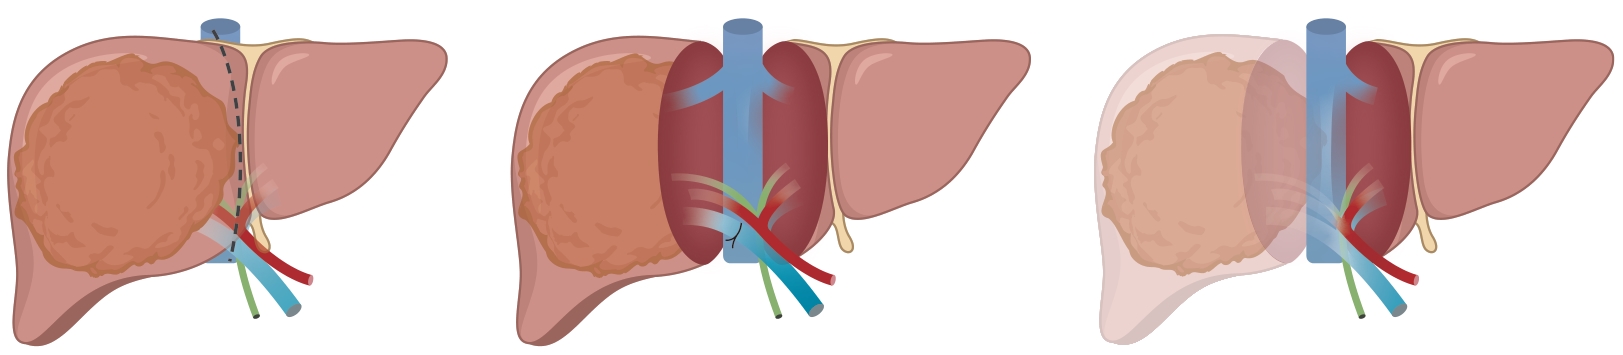

Large spontaneous splenorenal shunt embolization combined with anticoagulant therapy in treatment of portal vein thrombosis: A case report

Ju HUANG, Xiaoze WANG, Xuefeng LUO, Li YANG

2025, 41(8): 1639-1642. DOI: 10.12449/JCH250825

Abstract(504) HTML (172) PDF (3328KB)(67)

Abstract:

Portal vein thrombosis (PVT) is a common and severe complication in patients with liver cirrhosis, and alterations in portal hemodynamics are closely associated with the development of PVT. The presence of large spontaneous splenorenal shunt (SSRS) may lead to reductions in portal vein perfusion and blood flow velocity, which may compromise the anticoagulant effect on PVT. This article reports the treatment strategies of SSRS embolization combined with anticoagulant therapy that help to achieve complete recanalization of the portal vein; however, high-quality clinical studies are still needed to further validate and support the effectiveness of this strategy.